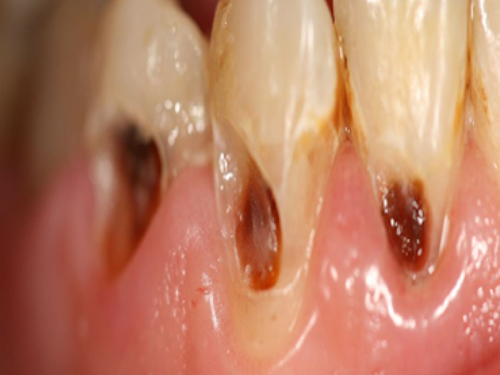

Early manifestation of decay is discolored surface of tooth. This is the demineralized portion of enamel (outer layer of tooth). This is mostly irreversible process requiring restorative treatment. If not treated at this stage, the decay may further involve dentin and pulp requiring more invasive procedure like root canal treatment.

It is suggested to get dental treatment done as early as possible. Progress of dental caries can be stopped by doing simple restorative treatment. If this is delayed, caries may progress involving pulp which requires root canal.